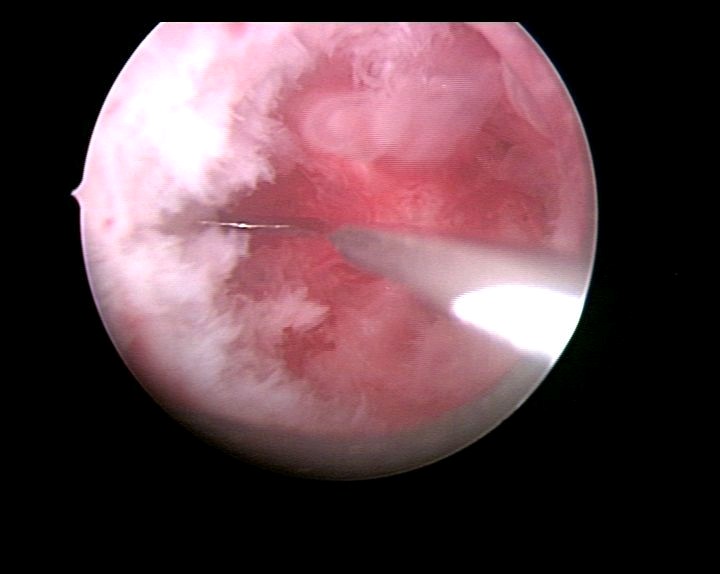

患者29岁,G1P0,人流术后闭经半年,2015年宫腔镜探查,发现宫颈管粘连,宫腔两侧粘连,冷刀(钩型刀)切割粘连,恢复宫腔形态,显露双侧输卵管开口。术后偶尔监测排卵试孕2年未孕,又过了1年,2018年不经意间自然妊娠,足月分娩。现40岁,G2P1。